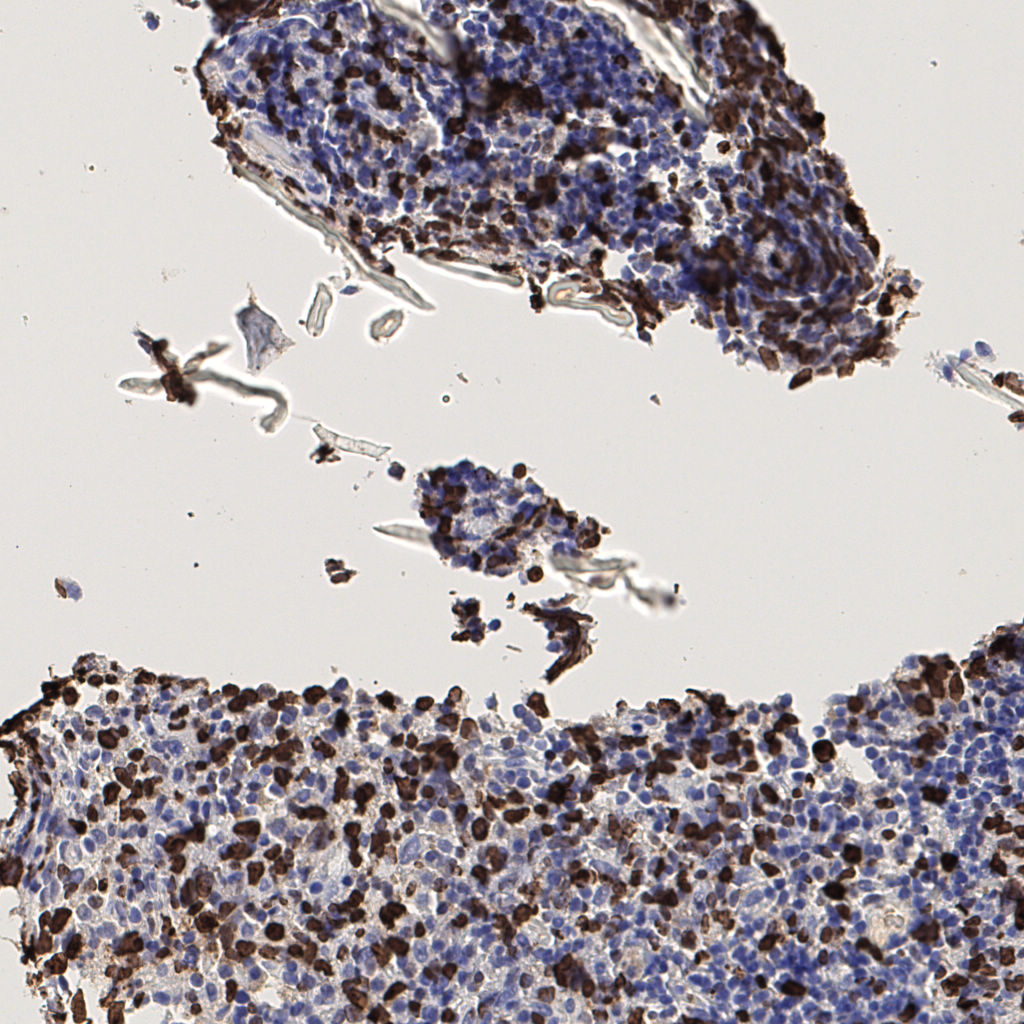

7.85%

Ki67 指数

阴 1104 阳 94

切片统计

总切片 1953

有效 288

已标记 288

有效率 15%